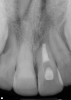

Figure 11  Clinical case of resorption related to the pressure of eruption (a progressive stress) on the upper right lateral incisor.

Figure 11

Figure 12  Clinical case of resorption related to the pressure of eruption (a progressive stress) on the upper right lateral incisor.

Figure 12

Figure 13  Clinical case of resorption related to the pressure of eruption (a progressive stress) on the upper right lateral incisor.

Figure 13

Figure 14  Clinical case of resorption related to the pressure of eruption (a progressive stress) on the upper right lateral incisor.

Figure 14

Figure 15  Clinical case of resorption related to the pressure of eruption (a progressive stress) on the upper right lateral incisor.

Figure 15